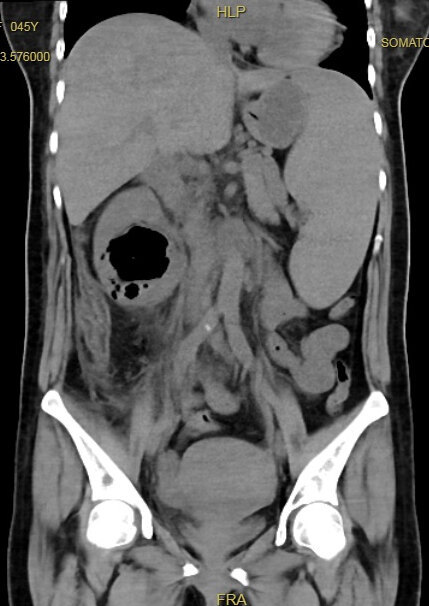

气肿性肾盂肾炎(EPN)是一种肾实质、集合系统与肾周的产气感染,是一种少见的肾脏严重急性感染性疾病,发展迅速,病情危重,死亡率比较高。主要以肾实质及周围组织弥漫性坏死、肾盏及肾周筋膜产生大量气体为特征。肺气肿性肾盂肾炎(EPN)是最严重的尿路感染类型之一。EPN是一种肾脏的急性坏死性感染,通常与高肾丢失率和死亡率有关。EPN感染的症状可以是非特异性的,但发热、胁腹痛和恶心的临床三联征是最常见的表现。最佳EPN治疗是有争议的,在早期研究中建议进行紧急肾切除术,而最近的证据支持更保守的方法。大肠杆菌、肺炎克雷伯菌和奇异变形杆菌是最常见的病原体。建议最初使用广谱抗生素,例如第三代或第四代头孢菌素类和碳青霉烯类药物。糖尿病、梗阻性尿路病和高血压是最常见的危险因素,往往需要同时治疗。紧急引流用较大尺寸的引流管指示,以达到更好的引流功能。CT引导比超声引导下的插入成功率更高。肾切除术应保留为保守治疗无效患者的最后手段。病因:1.未能有效规范控制血糖:糖尿病患者居多,控制不佳的高血糖,导致免疫力低下,为细菌生长提供有利条件。2.泌尿系统梗阻:主要为泌尿系结石或肿瘤导致。3.产气菌导致尿路混合性感染:主要为大肠埃希菌,这类细菌易酵解葡萄糖,产生大量乳酸和二氧化碳。4.免疫力低下:免疫缺陷、器官移植、大量激素使用患者。影像学检查:CT具有不受前后重叠、气体干扰等优越性,是目前诊断本病最佳方法之一,具有很高的敏感性、特异性及准确性,特别是CT多平面重建能够清晰显示泌尿系的梗阻部位和性质,可以明确病变的范围及严重程度,为临床诊断及治疗方案提供重要的参考价值。CT表现:肾脏体积增大,轮廓模糊,肾实质广泛破坏,并产生大量气体分布于肾实质、肾盂、输尿管及肾周间隙。累及肾周筋膜可形成肾周脓肿。实验室检查:白细胞计数明显增高,大部分糖尿病患者检测血糖明显升高或尿糖阳性,尿培养检出大肠杆菌,严重者出现肌酐明显升高等肾功能损害表现。临床表现:一般表现为腰痛、发热,部分并伴有寒战、呕吐,严重者可意识错乱、休克昏迷及发生急性肾衰竭等危急症状。查体肾叩痛是常见体征。抗生素:严重感染的治疗应始终从积极复苏开始,包括提供足够的静脉补液、供氧、胰岛素介导的血糖控制和广谱抗生素。经验性抗生素可降低革兰阴性全身性感染病例的死亡率。抗生素的选择必须对常见细菌有效,如大肠杆菌、肺炎克雷伯菌和奇异变形杆菌。其他致病微生物包括铜绿假单胞菌和肠球菌属。EPN的首选单药治疗应对这些最常见的病原体有效。推荐使用第三代或第四代头孢菌素和碳青霉烯类药物。联合治疗,例如使用阿米卡星和第三代头孢菌素,是一种替代策略,因为大肠杆菌、肺炎克雷伯菌和奇异卟啉单胞菌的耐药率较低。EPN可分为复杂性尿路感染或尿道脓毒症。在这两组中,通常建议治疗7-14天。但持续时间应与基础疾病的治疗密切相关。因此,我们建议在治疗这些患者时连续使用抗生素2周。在轻度疾病中,抗生素治疗至少1周仍然是必要的。引流:为了获得更好的引流,建议使用更大尺寸的引流管,最好在CT引导下插入,这比在超声引导下插入的成功率更高[33]。对于包裹性脓肿或多发性脓肿病例,应使用多根导管。引流管应保留在原位,直到随访CT显示EPN特征消退。建议在初始治疗后4-7周进行随访CT扫描,以评估结局并确定是否需要进一步的侵入性操作[34]。不幸的是,尽管有证据表明药物治疗结合充分引流可以提供更好的治疗结果,但由于缺乏比较研究,哪种类型的引流是最佳的仍然未知。由于大多数已发表的证据都是基于PCN的使用,因此药物治疗联合PCN可被视为轻度患者的标准疗法。切肾:在过去的20年里,EPN的治疗偏好发生了很大变化。在早期研究中,肾切除术被认为是EPN治疗的最佳治疗策略,一些报道显示,与手术治疗相比,药物治疗的死亡率更高。目前,EPN的首选治疗方法已从侵入性手术发展到更保守的方法,这可能是由于影像学检查方式和抗生素使用的改进以及引流技术的进步,这些因素共同将EPN的相关死亡率降低至21%;尽管肾切除术已成为不太受欢迎的一线治疗选择,但对于保守治疗失败的患者来说,它仍然是一种重要的治疗策略。对于EPN控制不佳且对药物治疗和经皮引流无效的患者,后续仍需行肾切除术。